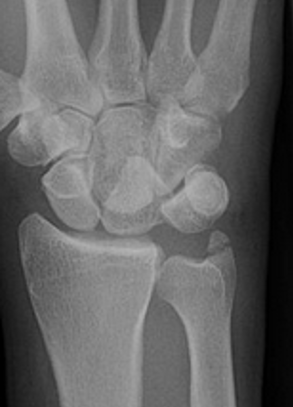

Gilula carpal arcs

Normally there are 3 smooth carpal arcs on PA xray

Arc I: Proximal cortical margins of proximal carpal row Arc II: Distal carpal margin of the proximal carpal row Arc III: Proximal cortices of the capitate and hamate |

AP X-ray

Disruption of Gilula's 3 smooth carpal arcs / triangular lunate

Normal versus disruputed Gilula's carpal arcs